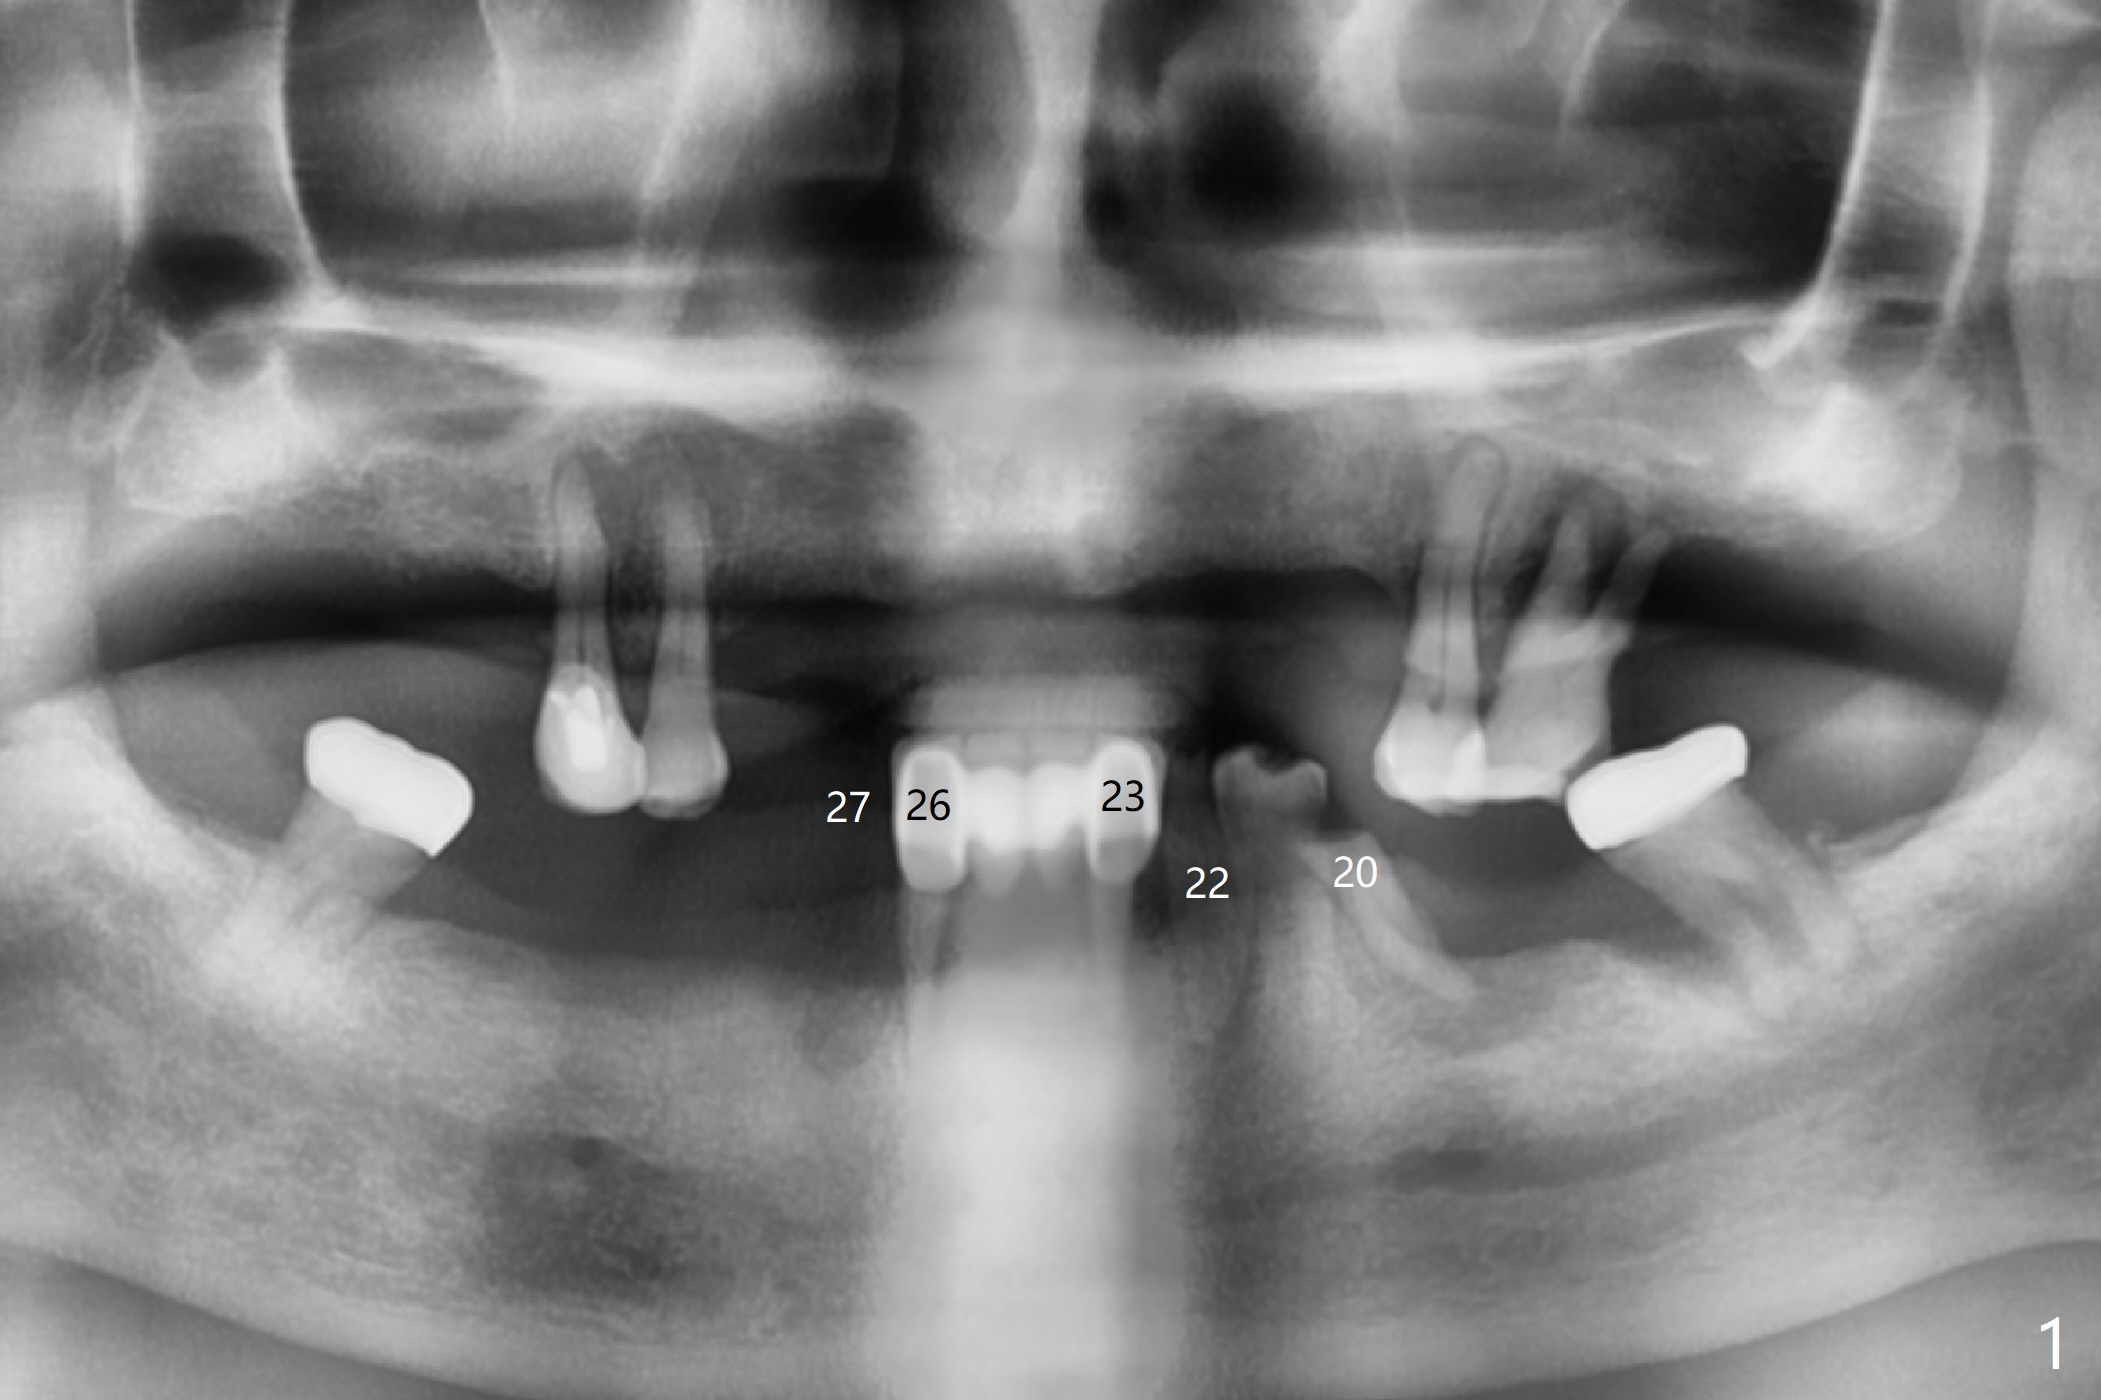

Abutments for Lower RPD

A 82-year-old man with poor dentition (upper and lower RPDs) returns to clinic for definitive treatment 2 weeks post socket preservation at #27 (with loss of the buccal plate, Fig.1). The bridge at #23-26 is mobile and to be removed. The tooth #22 appears to be restorable, but there is a buccal fistula (Fig.2 *). The root is out of the socket revealed by CBCT (Fig.5). Bone loss is severe at #20 (Fig.1,6). Three implants are going to be placed with guide at 27 or 26, 22 and 20 (Fig.3-6) with ball abutments for the lower RPD retention. Later the tooth #18 is found to be nonsalvageable.